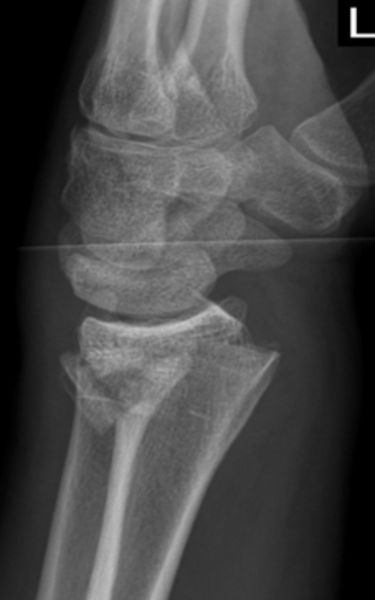

Besteht der klinische Verdacht auf eine distale Radiusfraktur wird zunächst ein Röntgenbild des Handgelenks in 2 Ebenen angefertigt. Bei schwereren Bruchformen sollte eine Computertomographie (CT) erfolgen um die weitere Therapie optimal planen zu können. In einigen Fällen, insbesondere bei Verdacht auf ligamentäre Begleitverletzungen (Verletzungen von Bandstrukturen im Handgelenks- und Handwurzelbereich), sollte eine Magnetresonanztomographie (MRT oder auch Kernspin genannt) durchgeführt werden.

Unterteilen lässt sich der Bruch nach dem Unfallhergang, nämlich ob der Bruch auf die ausgestreckte Hand (Extensionsfraktur oder auch Colles Fraktur) oder auf die gebeugte Hand (Flexionsfraktur oder auch Smith Fraktur) erfolgt ist. Daneben werden noch weitere Einteilungen vorgenommen, beurteilt wird hier, ob der Bruch ohne Gelenkbeteiligung, mit teilweise Beteiligung des Handgelenks  oder einer Trümmerfraktur des Handgelenks einhergeht.